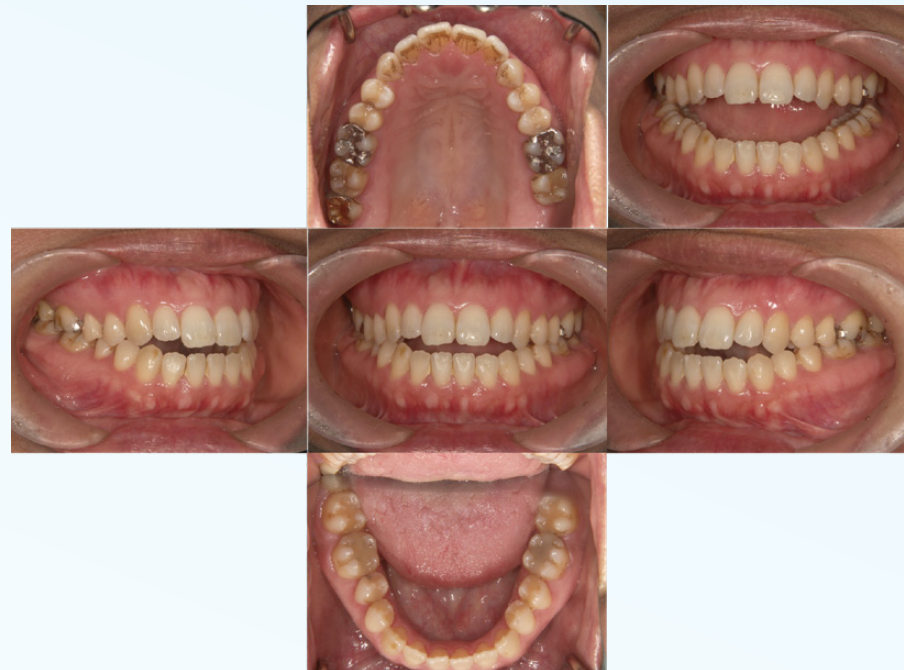

左下大臼歯部の急性炎症を主訴に来院(図16・17・18)。

緊急処置を行い、基礎資料を収集し問題点を抽出し、総合診断治療計画を立案し、患者に説明した。臼歯部に歯科治療が繰り返されている原因の一つに咬頭嵌合位が安定せず、咬合干渉が認められる病的咬合が挙げられる(図19)。臼歯部に応力が集中し、補綴装置やセメントが安定せず歯冠部からの漏洩によって根管内が感染していることも予測できる。包括的な見地から、咬合治療を行うために矯正治療の必要性を説明し承諾を得た。

矯正的診断は上下顎骨劣成長と骨格性開咬を伴うAngleⅡ級症例。矯正治療の目的は前歯の叢生の改善と適正な被蓋関係の確立。治療計画は上顎両側第一小臼歯を抜歯し、上顎前歯の叢生の改善と下顎両側第二小臼歯を抜歯し、下顎両側大臼歯を近心移動し、咬合高径を調整し前歯部の被蓋関係を改善する。初期治療にて炎症のコントロール、主に感染根管の再治療を行い(図20)、矯正治療に入る(図21)。矯正治療により歯のポジションが改善した後、プロビジョナルレストレーションにてリハビリテーションを検証し(図22)、最終補綴処置を行う(図23)。臼歯部の環境が改善された事で、臼歯への力の集中による失活歯の歯根破折の可能性の減少と根尖周囲の歯周組織の安定を確立できた。

<緊急処置後、初期治療前の口腔内写真と14枚法>

歯周病の程度は軽度。前歯部開口咬合状態を呈し、

既往歴はほぼ臼歯部に集中している

口腔内の傾向から臼歯に過度な負担があり、

さまざまな病態に至っていると推測する

(図19-1)

(図19-2)